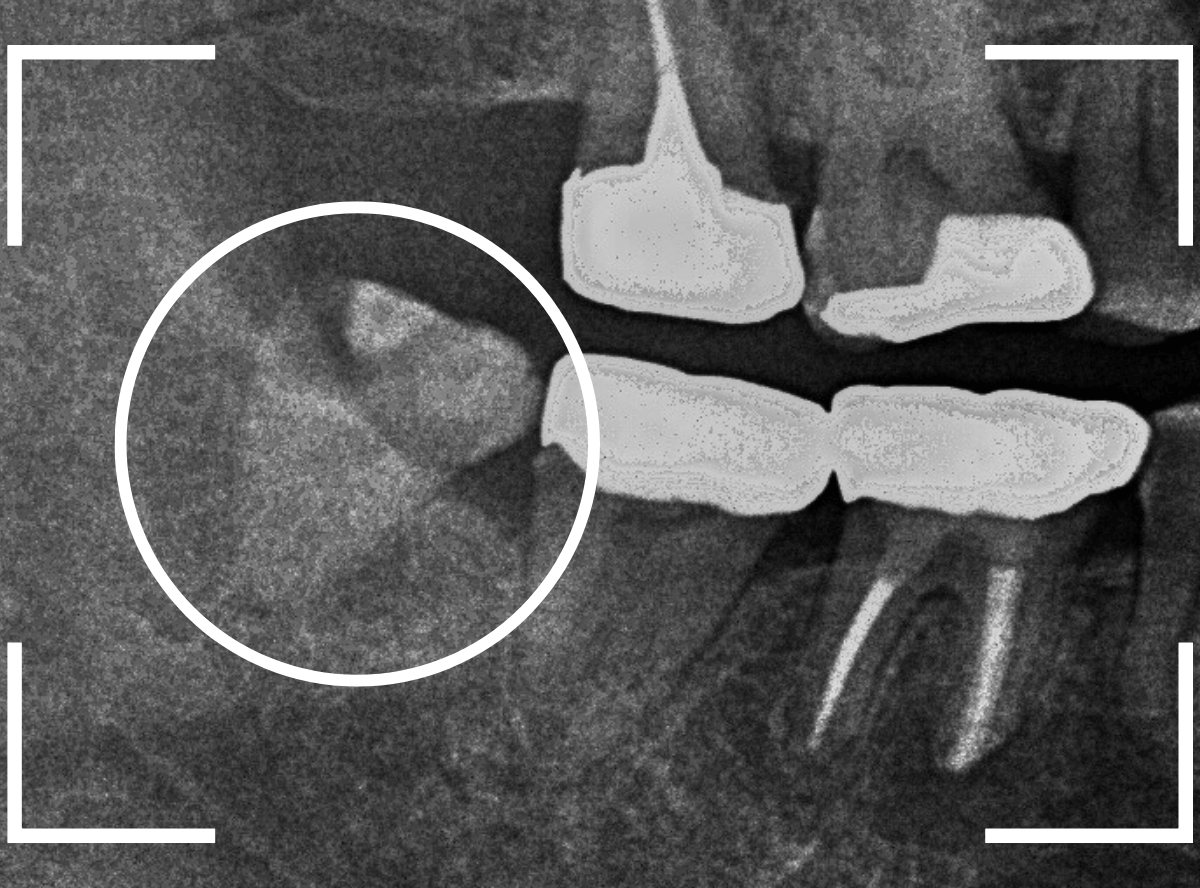

おやしらずの抜歯

ここでは、比較的簡単なおやしらずの抜歯の例を中心にご紹介します。

このようなおやしらず、あなたはありませんか?